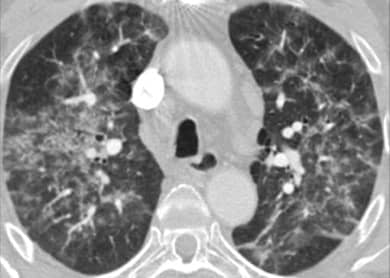

HP患者肺部发炎的CT扫描。致谢:M. Funke, J-M。Fellrath /欧洲呼吸杂志》上。